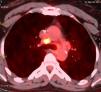

The patient received postoperative radiotherapy (45Gy) and hormonal therapy (tamoxifen) for 12 months. Two years later, new right axillary lymph node metastases were discovered and removed. One year later, chest CT showed in the mediastinum the presence of multiple lymph nodes with positive uptake value in the FDG PET scan (Fig. 1). The bronchoscopy was normal. Since standard uptake values (SUV) were low, a second FDG PET was performed 3 months later, showing stable lymph node growth. Mediastinoscopic biopsy of lymph nodes was performed, and it revealed non-caseating giant cells granulomas, consistent with sarcoidosis. The patient received corticoids, with good outcome.